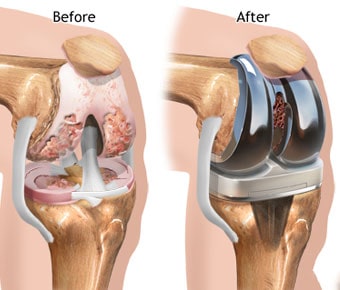

Dr. Amit Singh is an eminent Orthopaedic and Joint Replacement Surgeon in Mumbai. He has done MBBS and MS in Orthopaedics from the reputed Lokmanya Tilak Medical College and General Hospital (Sion Hospital). He has done a fellowship in Primary and Revision Hip and Knee Arthroplasty from South Korea. Dr. Amit Singh focuses on providing integrated orthopedic care at affordable prices to his patients. He always tries to make the pt understand the disease process, and how he can prevent himself from further complications and helps in selecting the best treatment option. He and his team are easily approachable.